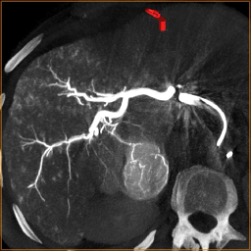

Высокое пространственное разрешение является ключевой сильной стороной ПДКТ, благодаря которой достигается четкая визуализация сосудов диаметром 250–300 мкм (0,25-0,30 мм) при проведении ПДКТ-артериографии (рис. 1). Такое высокое разрешение ПДКТ позволяет осуществлять прецизионный 3D-контроль установки стентов, микрокатетеров, тонких пункционных игл и других устройств непосредственно в рентгеноперационной (рис. 2). Пространственное разрешение характеризует точность воспроизведения малых структур в изоцентре и зависит от ряда факторов, таких как шаг пикселя, площадь сцинтиллятора, размер фокального пятна, геометрическое увеличение, стабильность системы во время сканирования, а также используемых фильтров реконструкции. Как уже было отмечено, применяемые в настоящее время a-Si:H/CsI:Tl ПДКТ-детекторы имеют высокие частотно-контрастные характеристики, благодаря конусовидному направлению света к каждому фотодиоду. Более толстый слой CsI улучшает поглощение, но увеличивает боковое размытие, снижающее контрастность, поэтому толщина и размер пикселя оптимизируются совместно [3, 4]. Пространственное разрешение напрямую зависит от режима считывания данных: при объединении (биннинге) пикселей, направленном на снижение шума и повышение контрастности получаемых изображений, пространственное разрешение прогрессивно снижается [35]. Как было показано в исследованиях на фантомах, ангиографическая установка Artis zee (Siemens Healthineers, Германия) при функции передачи модуляции (modulation transfer functions, MTF) в 10% достигает пространственного разрешения в 3,0 lp/mm при нативном считывании (1×1) и 1,5 lp/mm при биннинге 2×2, что превосходит разрешающую способность МСКТ (1,2–1,4 lp/mm в режимах высокого разрешения) [1, 35]. При использовании всех пикселей без их объединения разрешение может достигать почти 4,0 lp/mm, что соответствует возможности распознавания высококонтрастных деталей толщиной 130 мкм (0,13 мм) [35]. Переход на биннинг 2×2 удваивает размер эффективного пикселя с 154 мкм до 308 мкм, снижая MTF 10% вдвое, но повышая кадровую частоту до 30 кадров в секунду и минимизируя шум. При биннинге 4×4 (размер эффективного пикселя 616 мкм) разрешение падает до 1,0 lp/mm, однако возросшая скорость съёмки (60 кадров в секунду) и большее число проекций сокращает артефакты движения и улучшает контрастное разрешение, что чаще всего используется при визуализации органов брюшной полости и малого таза [35].

Рис. 1 (а-г). Церебральная ПДКТ-артериография бассейна правой общей сонной артерии, демонстрирующая возможность визуализации артерий диаметром 0,5 мм

Рис. 1а. Реконструкция всего артериального русла после проведения ПДКТ в режиме 20sDCT Head (Siemens Healthineers, Германия) с введением 60 мл контрастного препарата со скоростью 2 мл/с (в течение 30 с) и задержкой сканирования 10 с

Рис. 1б. Визуализация правой центральной артерии сетчатки глаза диаметром 0,5 мм в режиме MIP (тонкие срезы) у того же пациента

Рис. 1в-г. Визуализация той же артерии и дренирующих вен в косых проекциях (MIP) с использованием более толстых срезов.